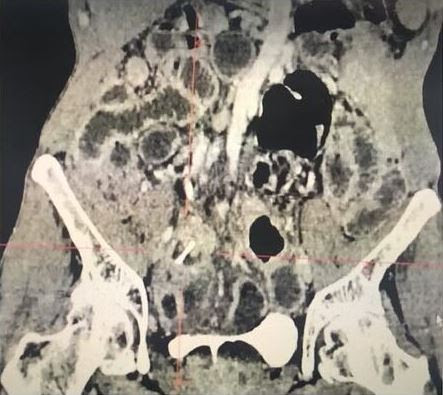

Foto: Mehdi TM, Neirouz K, Souhir N, et al

Além disso, ele não conseguia se lembrar do que poderia ter comido anteriormente. Mas após a realização de uma tomografia computadorizada foi encontrado um pedaço de osso de frango de dois centímetros atravessando o seu apêndice. Então, os médicos descobriram que ele havia comido frango em um churrasco com colegas de trabalho.